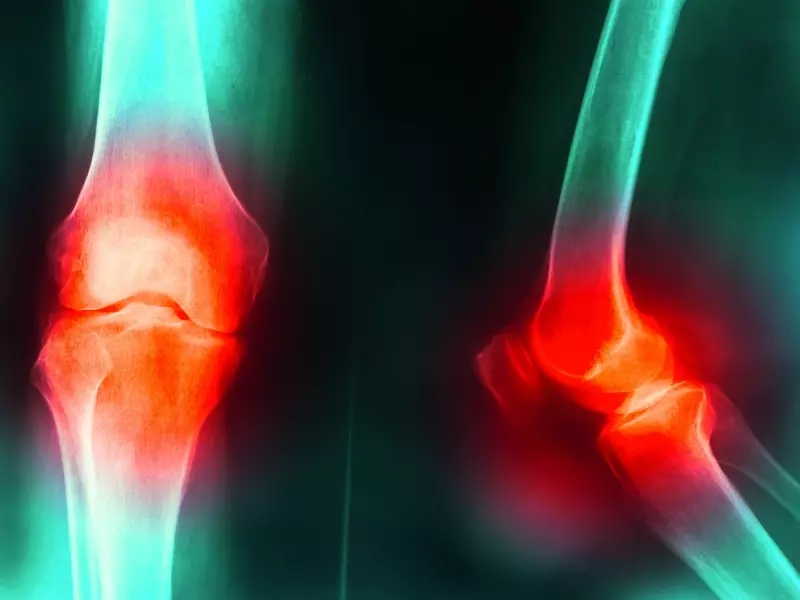

Zespół bocznego przyparcia rzepki należy do grupy dysfunkcji bólowych stawu kolanowego i jest główną przyczyną dolegliwości bólowych zlokalizowanych po stronie zewnętrznej. W pierwszej fazie tej choroby odczucia bólowe i dotykowo wrażliwe struktury okołokolanowe są jedynym symptomem mogącym nakierować na prawidłowe rozpoznanie. Na tym etapie nie ma widocznych zmian struktury rzepki i jej okolicznych struktur miękkich w badaniach obrazowych. Stąd też rzadko choroba jest prawidłowo rozpoznawana przez diagnostów i często pomijana w terapiach fizjoterapeutycznych.

Kolejny etap rozwoju dysfunkcji bardzo często charakteryzuje się zmianą w obrębie chrząstki stawowej rzepki nazywaną klinicznie chondromalacją rzepki. Dlatego w 2010 r. w Polsce rozpoznawalność kliniczna zespołu bocznego przyparcia rzepki była na poziomie 1 na 100 pacjentów z przewlekłym zewnętrznym bólem stawu kolanowego. W tym czasie pacjentów z chondromalacją rzepki I i II stopnia było 50 na 100 pacjentów z zespołem bólowym kolana. Obecnie te proporcje zamieniają się i znaczy to tyle, że w większości przypadków są to te same jednostki oceniane z dwóch różnych perspektyw.

Perspektywa funkcjonalna, inaczej zwana przyczynową, określa dysfunkcję jako zespół bocznego przyparcia rzepki, natomiast perspektywa skutkowa, inaczej zwana strukturalną, jako chondromalację rzepki. O ile w przypadku uszkodzonej chrząstki leczenie wydaje się problematyczne i oparte na wiskosuplementacji, o tyle zatrzymanie procesu patofizjologicznego powstrzyma zwiększanie symptomów, a z czasem zmniejszy ból.